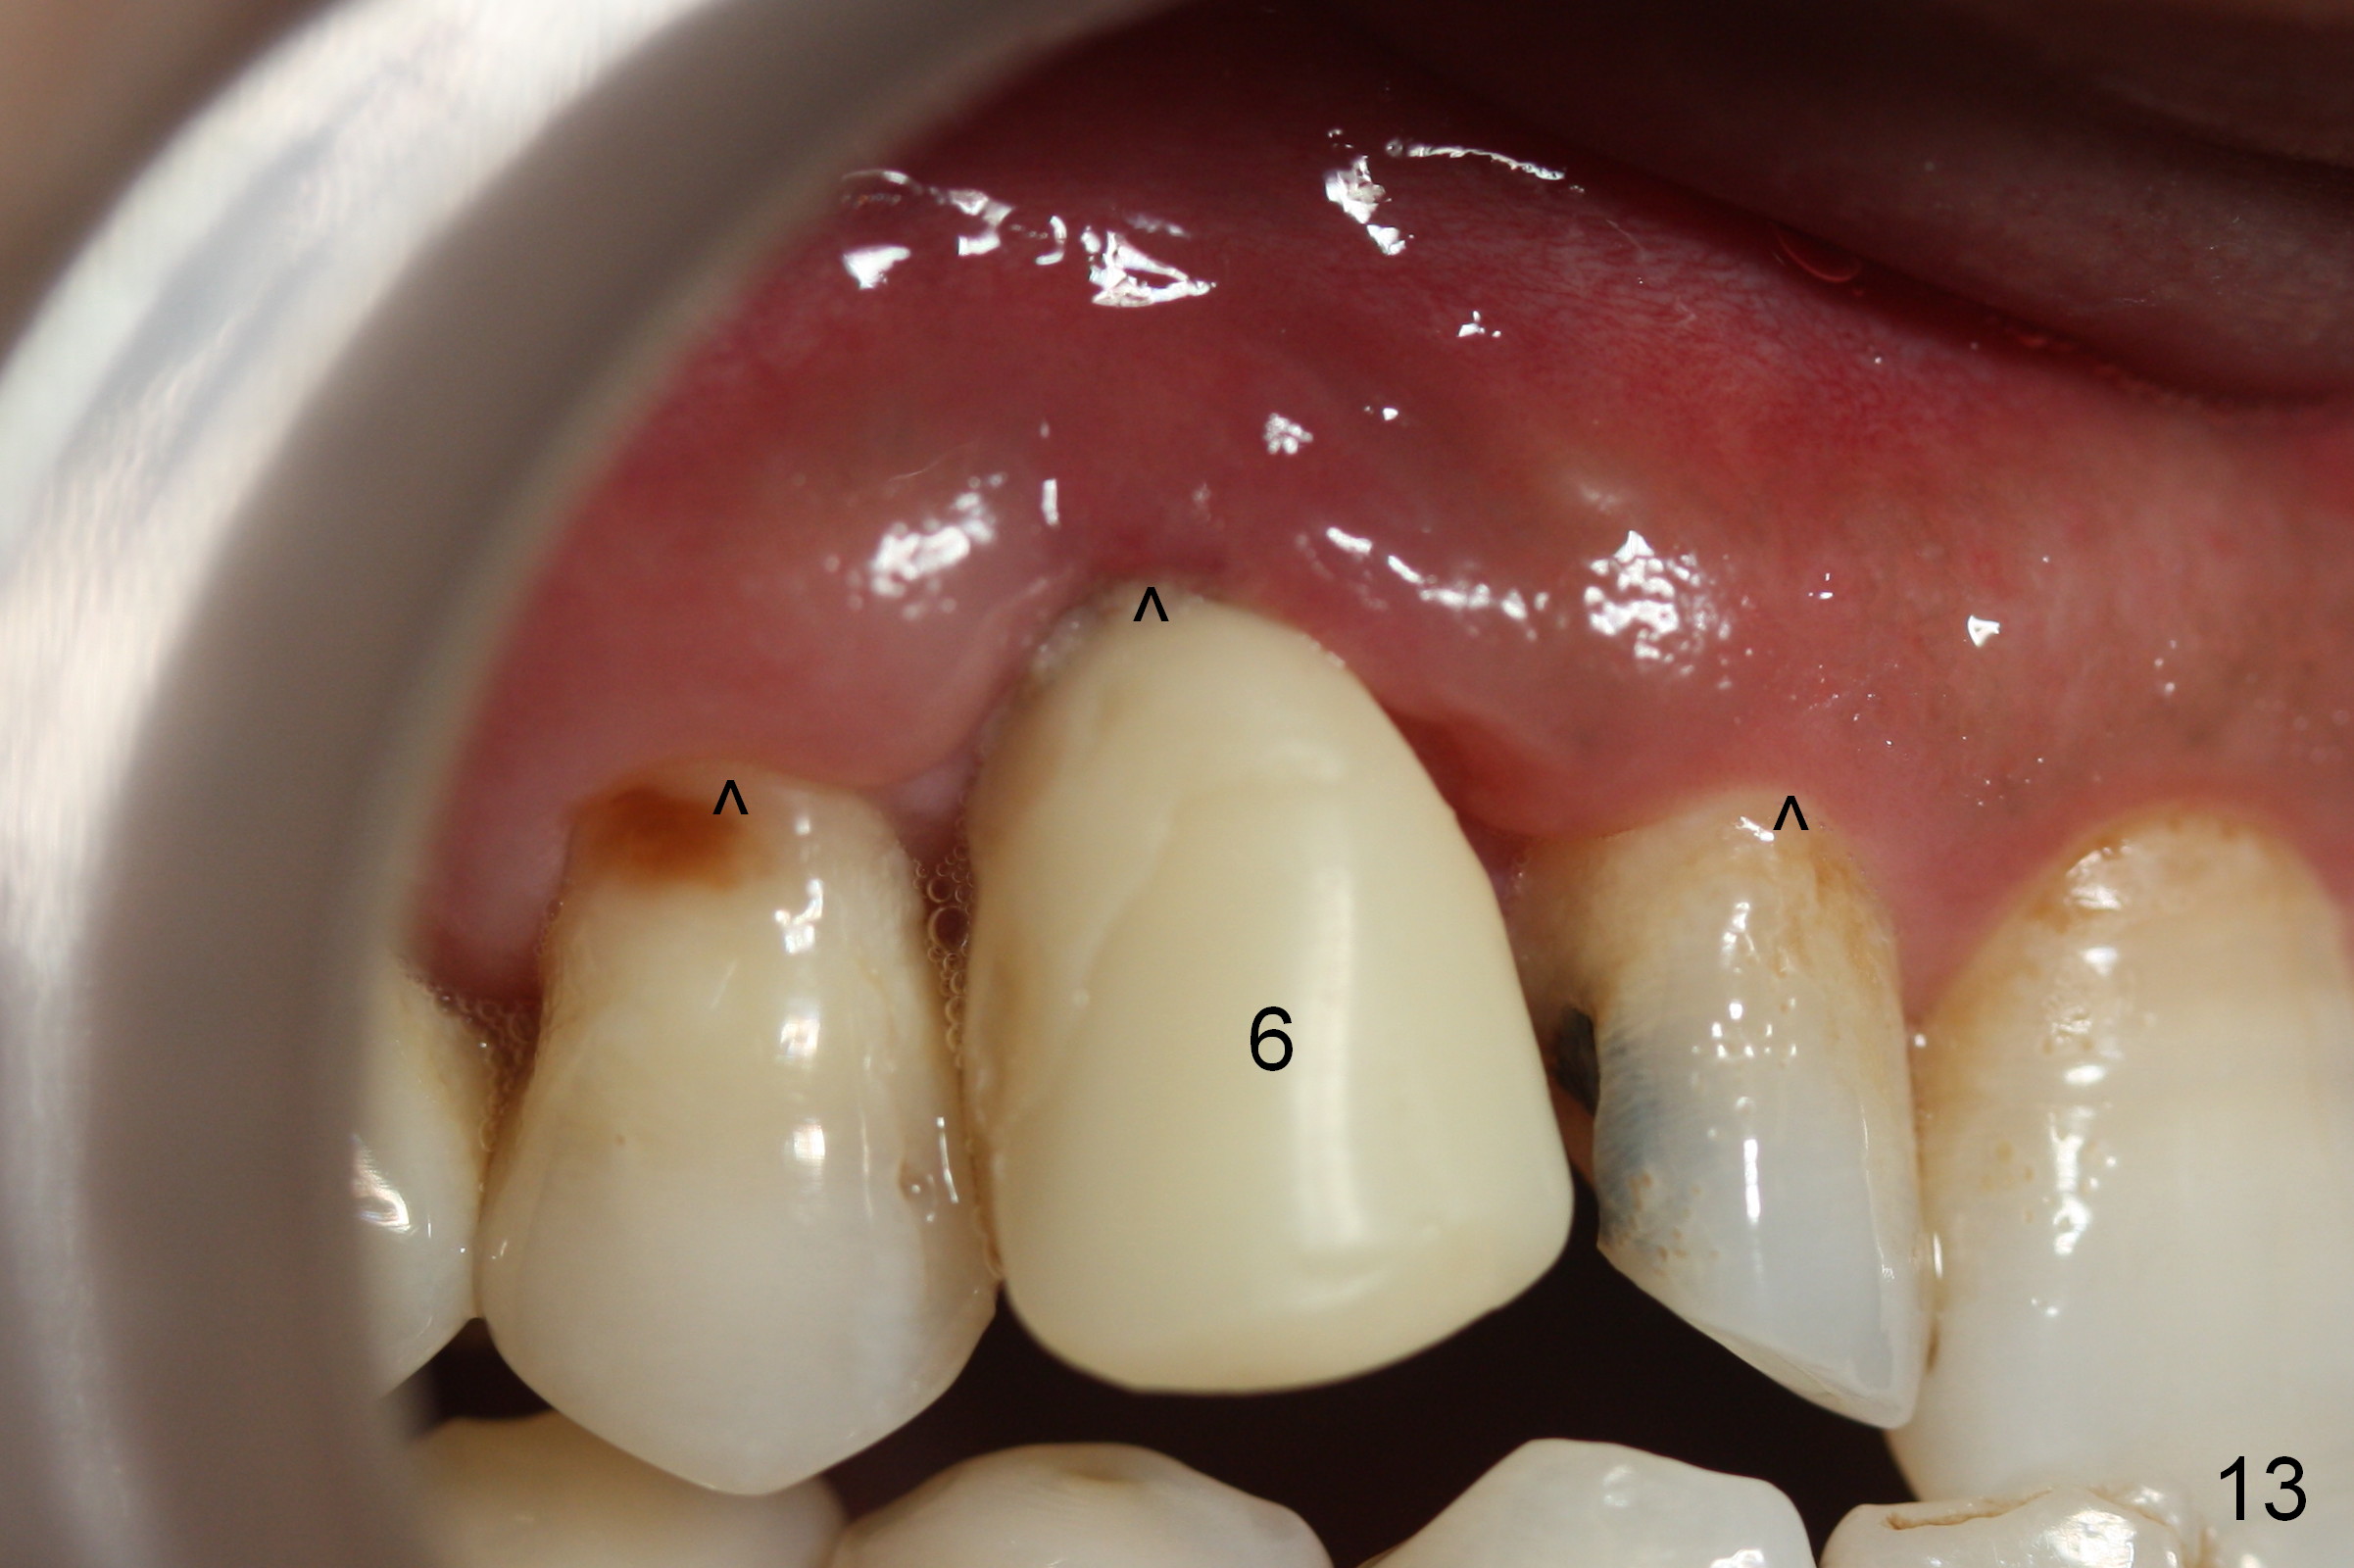

The patient returns 1.5 months postop. The provisional margin is much higher than that of the neighboring teeth (Fig.12,13: #6), unlike the opposite side (Fig.12: #11). When the provisional is removed, the implant margin is at the same level as that of the neighboring teeth (Fig.14 arrowheads). The implant margin is slightly extended apically (Fig.15 ^) prior to seating of the modified provisional. When the provisional is seated, its margin (Fig.16 ^) is at the implant margin; the gingival margin (*) is free and expected to move coronally by itself.